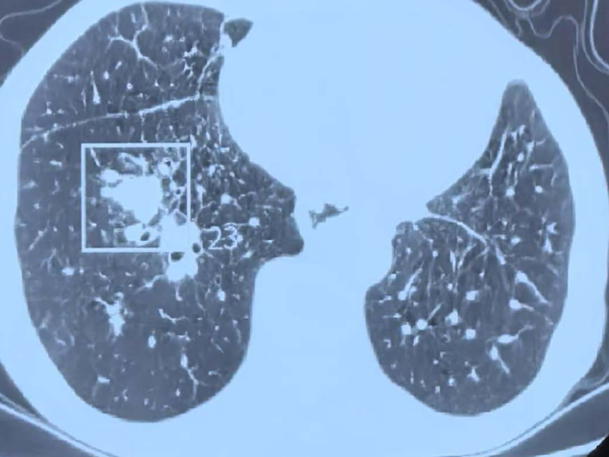

据悉,该男性患者肿瘤病史错综复杂且极为危重。此前,他先后被确诊患有喉癌、食管癌,在历经手术治疗后,又不幸罹患淋巴瘤。不仅如此,右肺还出现多发转移病灶,虽接受过肺部消融治疗且效果良好,但此次复查却如同一记重击——右肺下叶血管池内出现一处食管癌肺转移灶,最大直径达2.1厘米。

禁区操作精准消融突破困境

在麻醉团队的全力保障下,陶冀教授团队凭借丰富的临床经验和精湛的技术,采取左侧卧位,运用单针精准分段穿刺技术,如同一位技艺高超的工匠,将消融针尖精准无误地置入病灶核心。术中,他们以30—40W的中低功率进行消融,持续9分钟后,谨慎退针并补充消融,通过两个精心设计的消融循环,确保消融范围完全覆盖病灶,实现肿瘤的彻底灭活。手术过程顺利,术中无出血,仅出现少量气胸,经置管抽气后迅速缓解,重要血管与支气管均得到妥善保护。